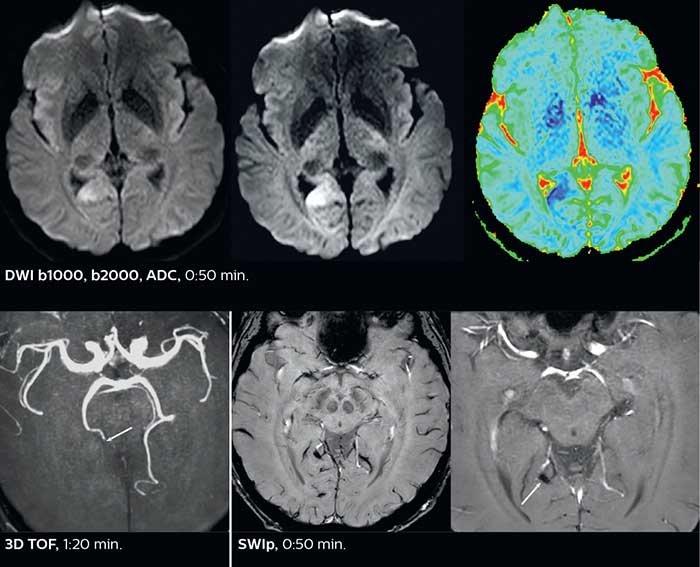

Dr. Savatovsky appreciates the improvements and flexibility that Elition with Compressed SENSE and MultiBand SENSE provides, particularly for stroke patients. “For stroke, it allows us to cut about 5 minutes off of our stroke protocol, or to keep the same acquisition time and get more insights.” The ability to perform more sequences can help in making a swift and confident diagnosis. “For example, our stroke cases usually include the regular sequences that every center does (b1000 diffusion, FLAIR, time-of-flight angiography), but we also image supra aortic vessels, and we can replace a gradient echo sequence with a fast 50-second susceptibility-weighted sequence, and all of this doesn’t add much time. because all the regular sequences are accelerated on Elition.” “The time savings with Compressed SENSE and MultiBand SENSE make it easier to add sequences to give us additional insights. Depending on the context and the first results, we might add a DSC perfusion to assess the ischemic penumbra, an ASL perfusion to help find an alternative cause in case of normal diffusion, or add a high-resolution T1 sequence for a stroke patient, to quickly assess wall imaging in emergency cases. The additional sequences can help improve patient management, because we can already consider some alternative diagnoses if the morphological MRI is normal.”

Using MultiBand SENSE allowed the staff to improve their diffusion quality. “Our diffusion sequence was already fast before, about 40 seconds. Now with Elition, it still lasts 40 seconds, but we improved the spatial resolution by 0.2 mm and use high b-values to be more sensitive to visualize changes related to acute stroke,” says Dr. Savatovsky. “We now also developed a high resolution DTI sequence (1.3 x 1.3 x 2 mm) that can be reformatted and takes 2 to 5 minutes depending on the coverage. We use it every time we have a doubt, or when we expect the diffusion to be abnormal but don’t see that on the fast sequence. We occasionally spot small ischemic infarctions that would not have been visible with the regular diffusion sequence.”

This is an example of acute ischemic stroke with distal occlusion of the right posterior cerebral artery. Note the improved visibility of the ischemic territory on the diffusion weighted image with high b-value. The 3D FLAIR shows a distal PCA occlusion. The fast SWIp depicts the thrombus on the isolated second echo image. The total scan time (including SmartBrain, preparations and a fast 3D T1w TSE Gd) is 8:00 minutes.